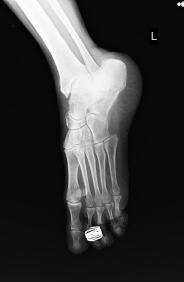

CLINICAl IMAGES